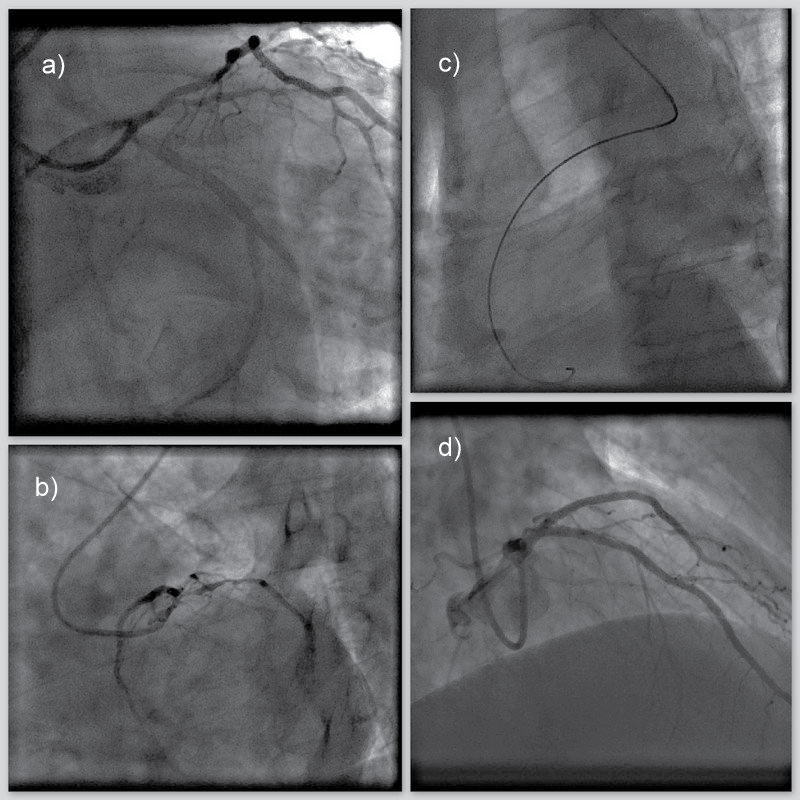

67-year-old man with history of arterial hypertension and type 2 diabetes mellitus was admitted to hospital due to elective coronary angiography. Six weeks before he was admitted due to acute ST elevation myocardial infarction (STEMI) of inferior wall. Coronary angiography, using left transradial access, revealed occlusion of proximal right coronary artery (RCA) and primary PCI with implantation of two drug-eluting stents (DES) was done. Coronary angiography also revealed significant bifurcation stenosis in proximal LAD and ostial first diagonal branch (D1) (Medina 1,0,1) [9] whereas left circumflex artery (LCx) had no stenosis (Figure 1a and Figure 1b). During procedure right transradial access was used due to pathological Allen's test on the left arm as well as weaker pulses bilaterally in the groins.

Figure 1a: Coronary angiography - initial recording (left anterior oblique 15° + caudal 40° projection) Bifurcation stenosis of left anterior descending artery (LAD) and first diagonal branch (D1) - classification Medina 1,0,1.

Figure 1b: Coronary angiography - initial recording (Left anterior oblique 40° + caudal 20° projection) Bifurcation stenosis of left anterior descending artery (LAD) and first diagonal branch (D1) - classification Medina 1,0,1.

Figure 1c: Coronary angiography - initial recording (left anterior oblique 30°). Positioning of guiding cathether revealed aberrant right subclavian artery (ARSA)

Figure 1d: Coronary angiography - final result after percutaneous coronary intervention (Right anterior oblique 40° + caudal 30° projection).

Final result after percutaneous coronary intervention with placement of one stent in left anterior descending artery (LAD) and two stents in first diagonal branch (D1) achieving TIMI III flow grade and myocardial blush grade 3 both in main and side branch. View Figure 1

Vascular access was obtained with regular radial 6Fr sheath (Radiofocus introducer II transradial Terumo, Tokyo, Japan) and then we advanced into the descending aorta with standard J-type guidewire 0.035 (BBraun). The advancement of the guiding catheter into the ascending aorta was difficult, so we performed aortography which revealed ARSA (Figure 1c). Due to peripheral vascular status, the procedure was continued without changing arterial access. Reaching ascending aorta was attempted with several cathethers, but we succeeded with Internal Mammary cathether 5Fr (Optitorque, Terumo Tokyo, Japan) and hydrophilic 0.035 wire (Radiofocus guidewire M standard type 0.035). Advancement was facilitated with deep-breath maneuver. Afterwards, hydrophilic guidewire was exchanged to support 0.035 guidewire (SupraCore 0.035, Abbott Vascular California, USA) and then 6Fr guiding cathether (EBU 6/3.5, Medtronic, Minneapolis, Minnesota, USA) was introduced and placed to left coronary ostium. Distal LAD na D1 was wired with standard working horse wires (BMW Elite; Abbott Vascular, California, USA). After balloon predilatation (Trek 2.5/20 mm and Trek 2.0/12 mm; Abbott Vascular, California, USA), first DES (Xience 2.5/18 mm; Abbott Vascular, California, USA) was implanted to distal LAD. Second and third DES (Xience 2.75/23 mm to D1 and Xience 3.0/18 mm to LAD; Abbott Vascular, California, USA) was implanted to bifurcation lesion LAD/D1 using culotte technique [8]. During procedure three times proximal optimization technique was performed with non-compliant (NC) 3.5 × 8 mm balloon (NC Trek Abbott Vascular, California, USA), and kissing postdilatation was perfomed with 3.0 × 12 mm NC balloon (NC Trek Abbott Vascular, California, USA) and 3.0 × 15 mm NC balloon (NC Trek Abbott Vascular, California, USA). The intervention resulted in normal TIMI III flow grade and myocardial blush grade III (Figure 1d). 263 mL of radiographic contrast medium (Visipaque 320, GE Healthcare, General Electrics Company, Chicago, Illinois, USA) was used and total of 13923 centiGycm2 X-ray exposure. Postprocedurally, patient was verticalized after 6 hours and he had no discomfort. Postprocedural CT angiography of the aorta was done revealing the absence of truncus brachiocephalicus, with common carotid ostium, regular position of left subclavian artery and confirming anomalous ostium of right subclavian artery as most distal branch on aortic arch with retrooesophageal course towards right arm (Figure 2). Patient was released from the hospital on the 3rd postprocedural day with normal vascular status of the right arm as well as normal haemoglobin, serum creatinine levels and no signs of bleeding.